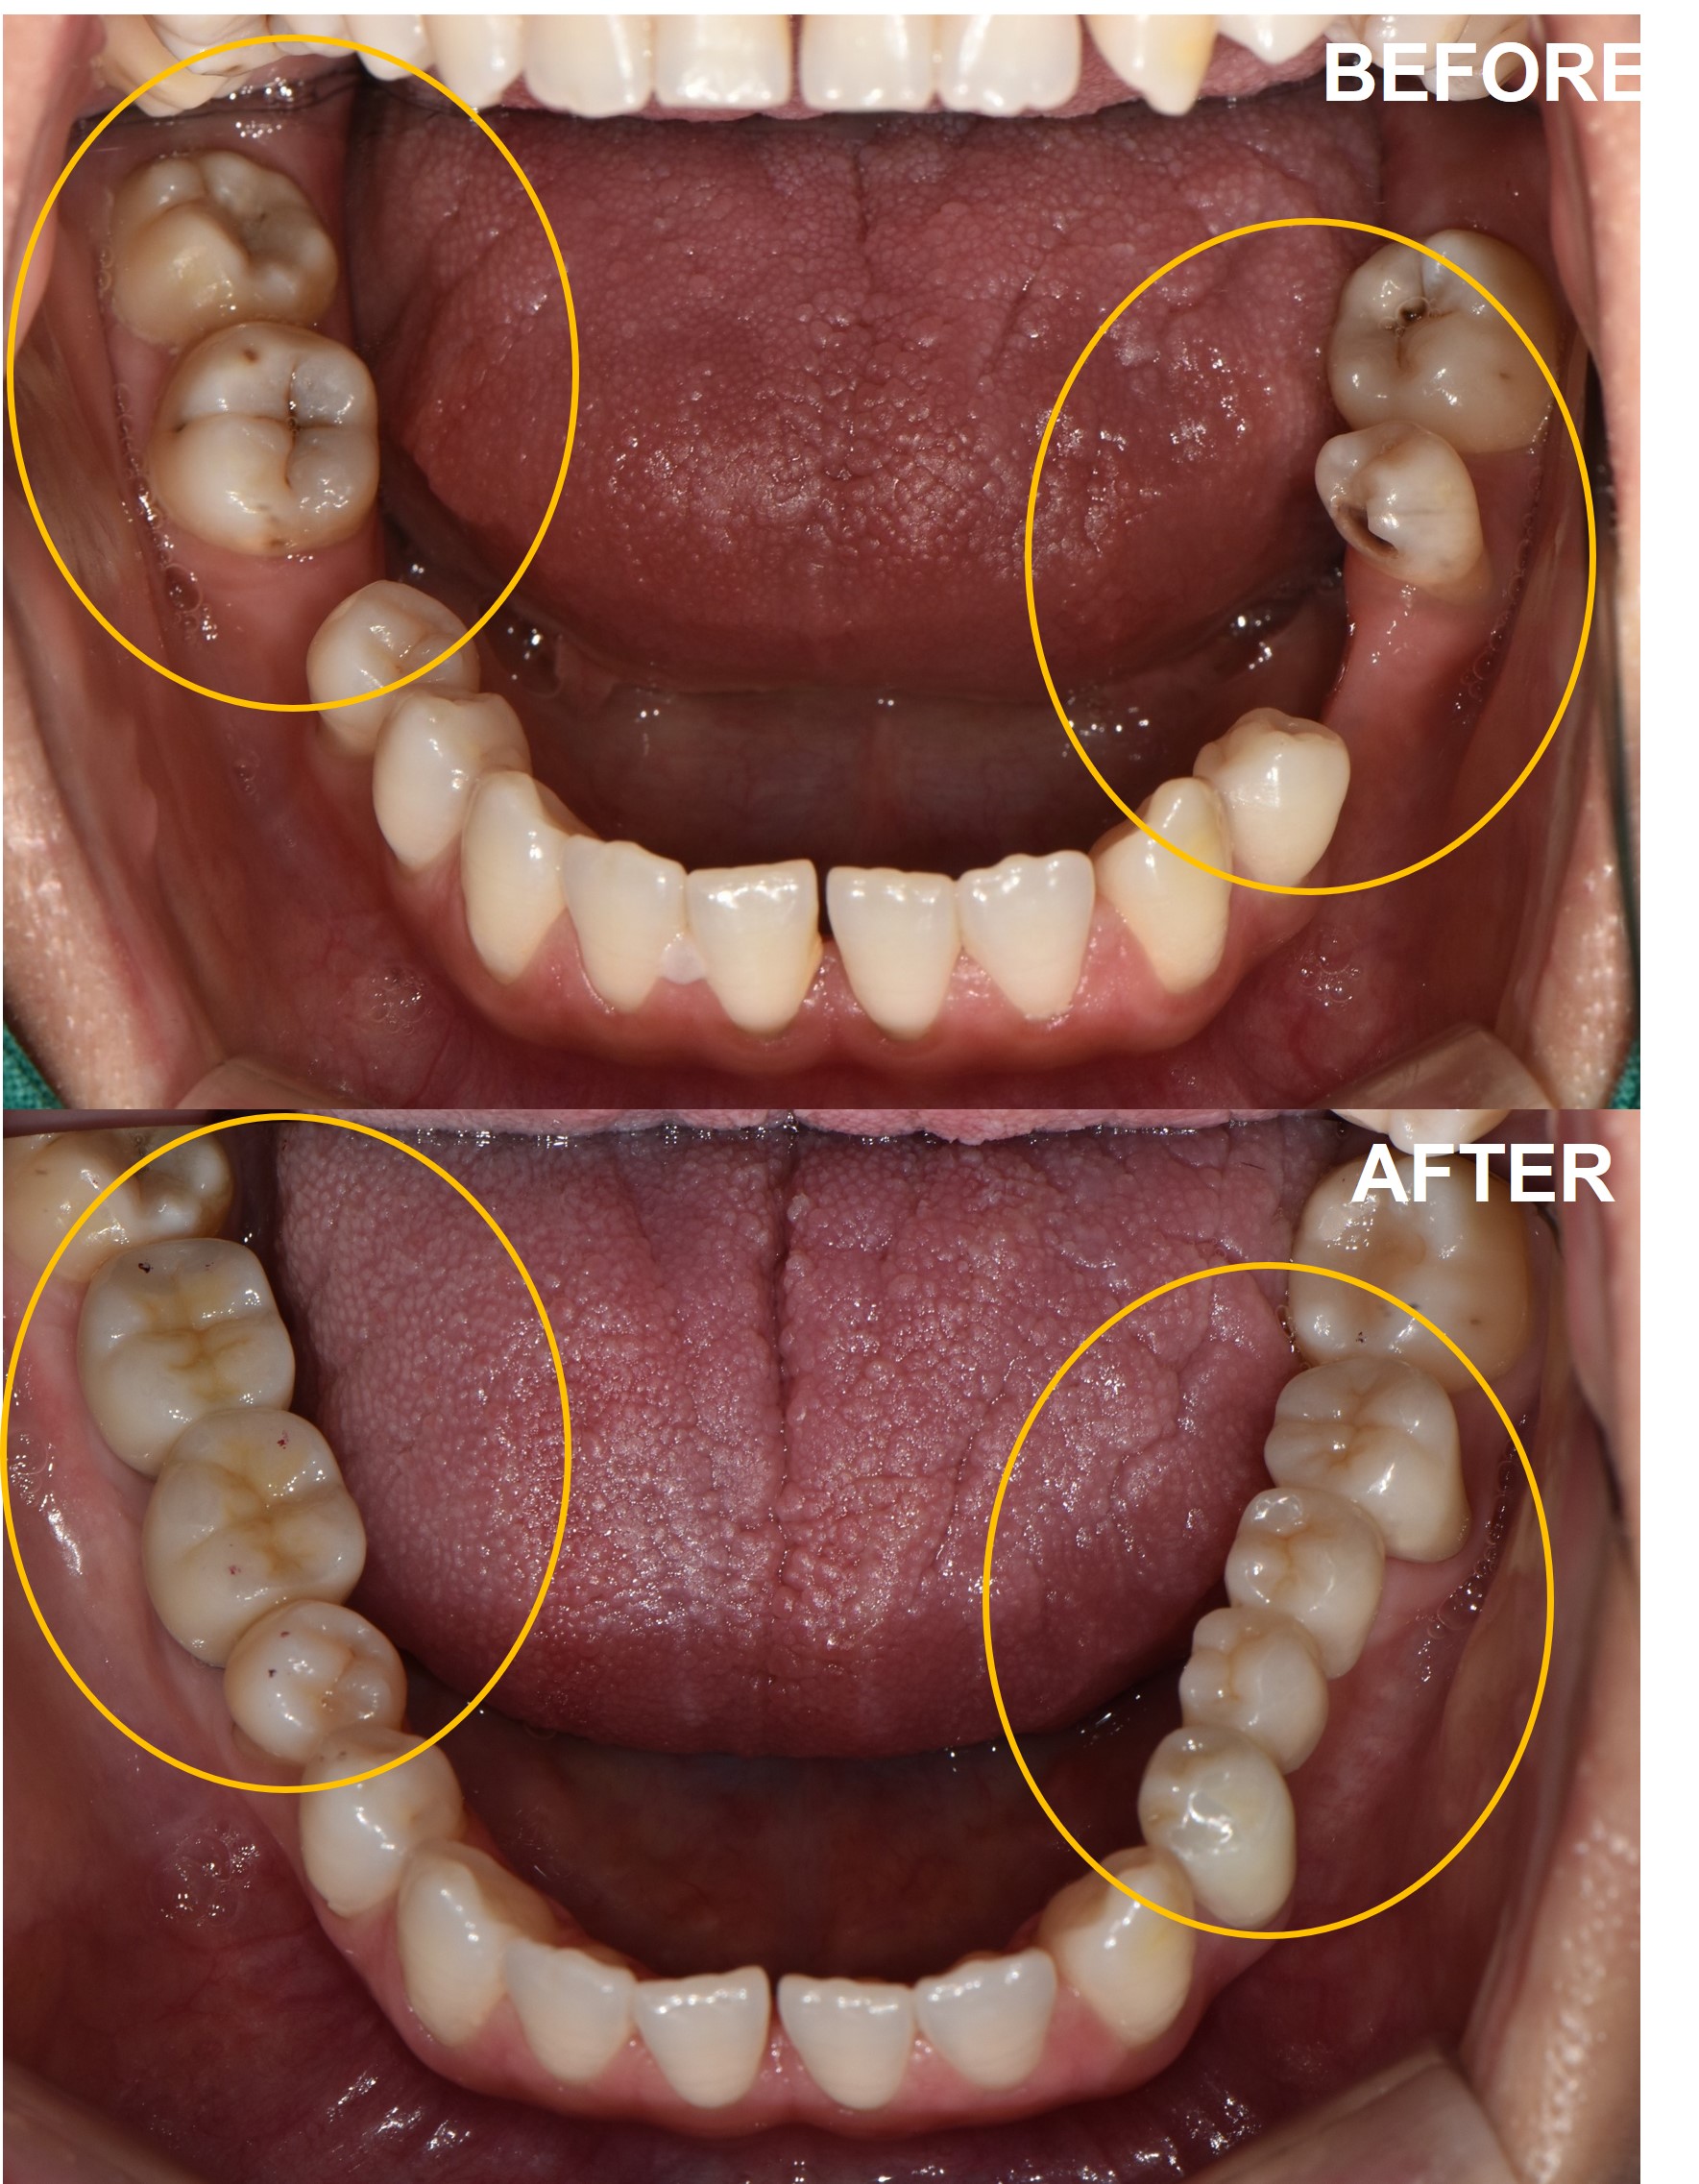

검단가온치과 임플란트 브릿지 치료 전후 구강 사진

검사부터 최종 보철까지 총 6단계로 진행되며, 일반적인 경우 전체 치료 기간은 약 3~5개월입니다.

1단계 검사 및 CT: 파노라마 촬영 후 필요 시 CT로 잇몸뼈 상태를 확인합니다.

2단계 발치·뼈이식 (필요 시): 케이스에 따라 발치나 뼈이식을 먼저 진행합니다.

3단계 임플란트 식립: 잇몸뼈에 인공 치근을 심는 수술입니다.

4단계 골유착 및 치유: 뼈와 임플란트가 단단히 결합되는 기간으로 약 2~4개월 소요됩니다.

5단계 지대주 및 크라운 보철: 임플란트와 크라운을 연결하는 지대주를 장착하고, 최종 인공 치아를 올립니다.

6단계 정기검진 및 유지관리: 3~6개월 주기로 정기검진과 구강위생 관리를 받습니다.